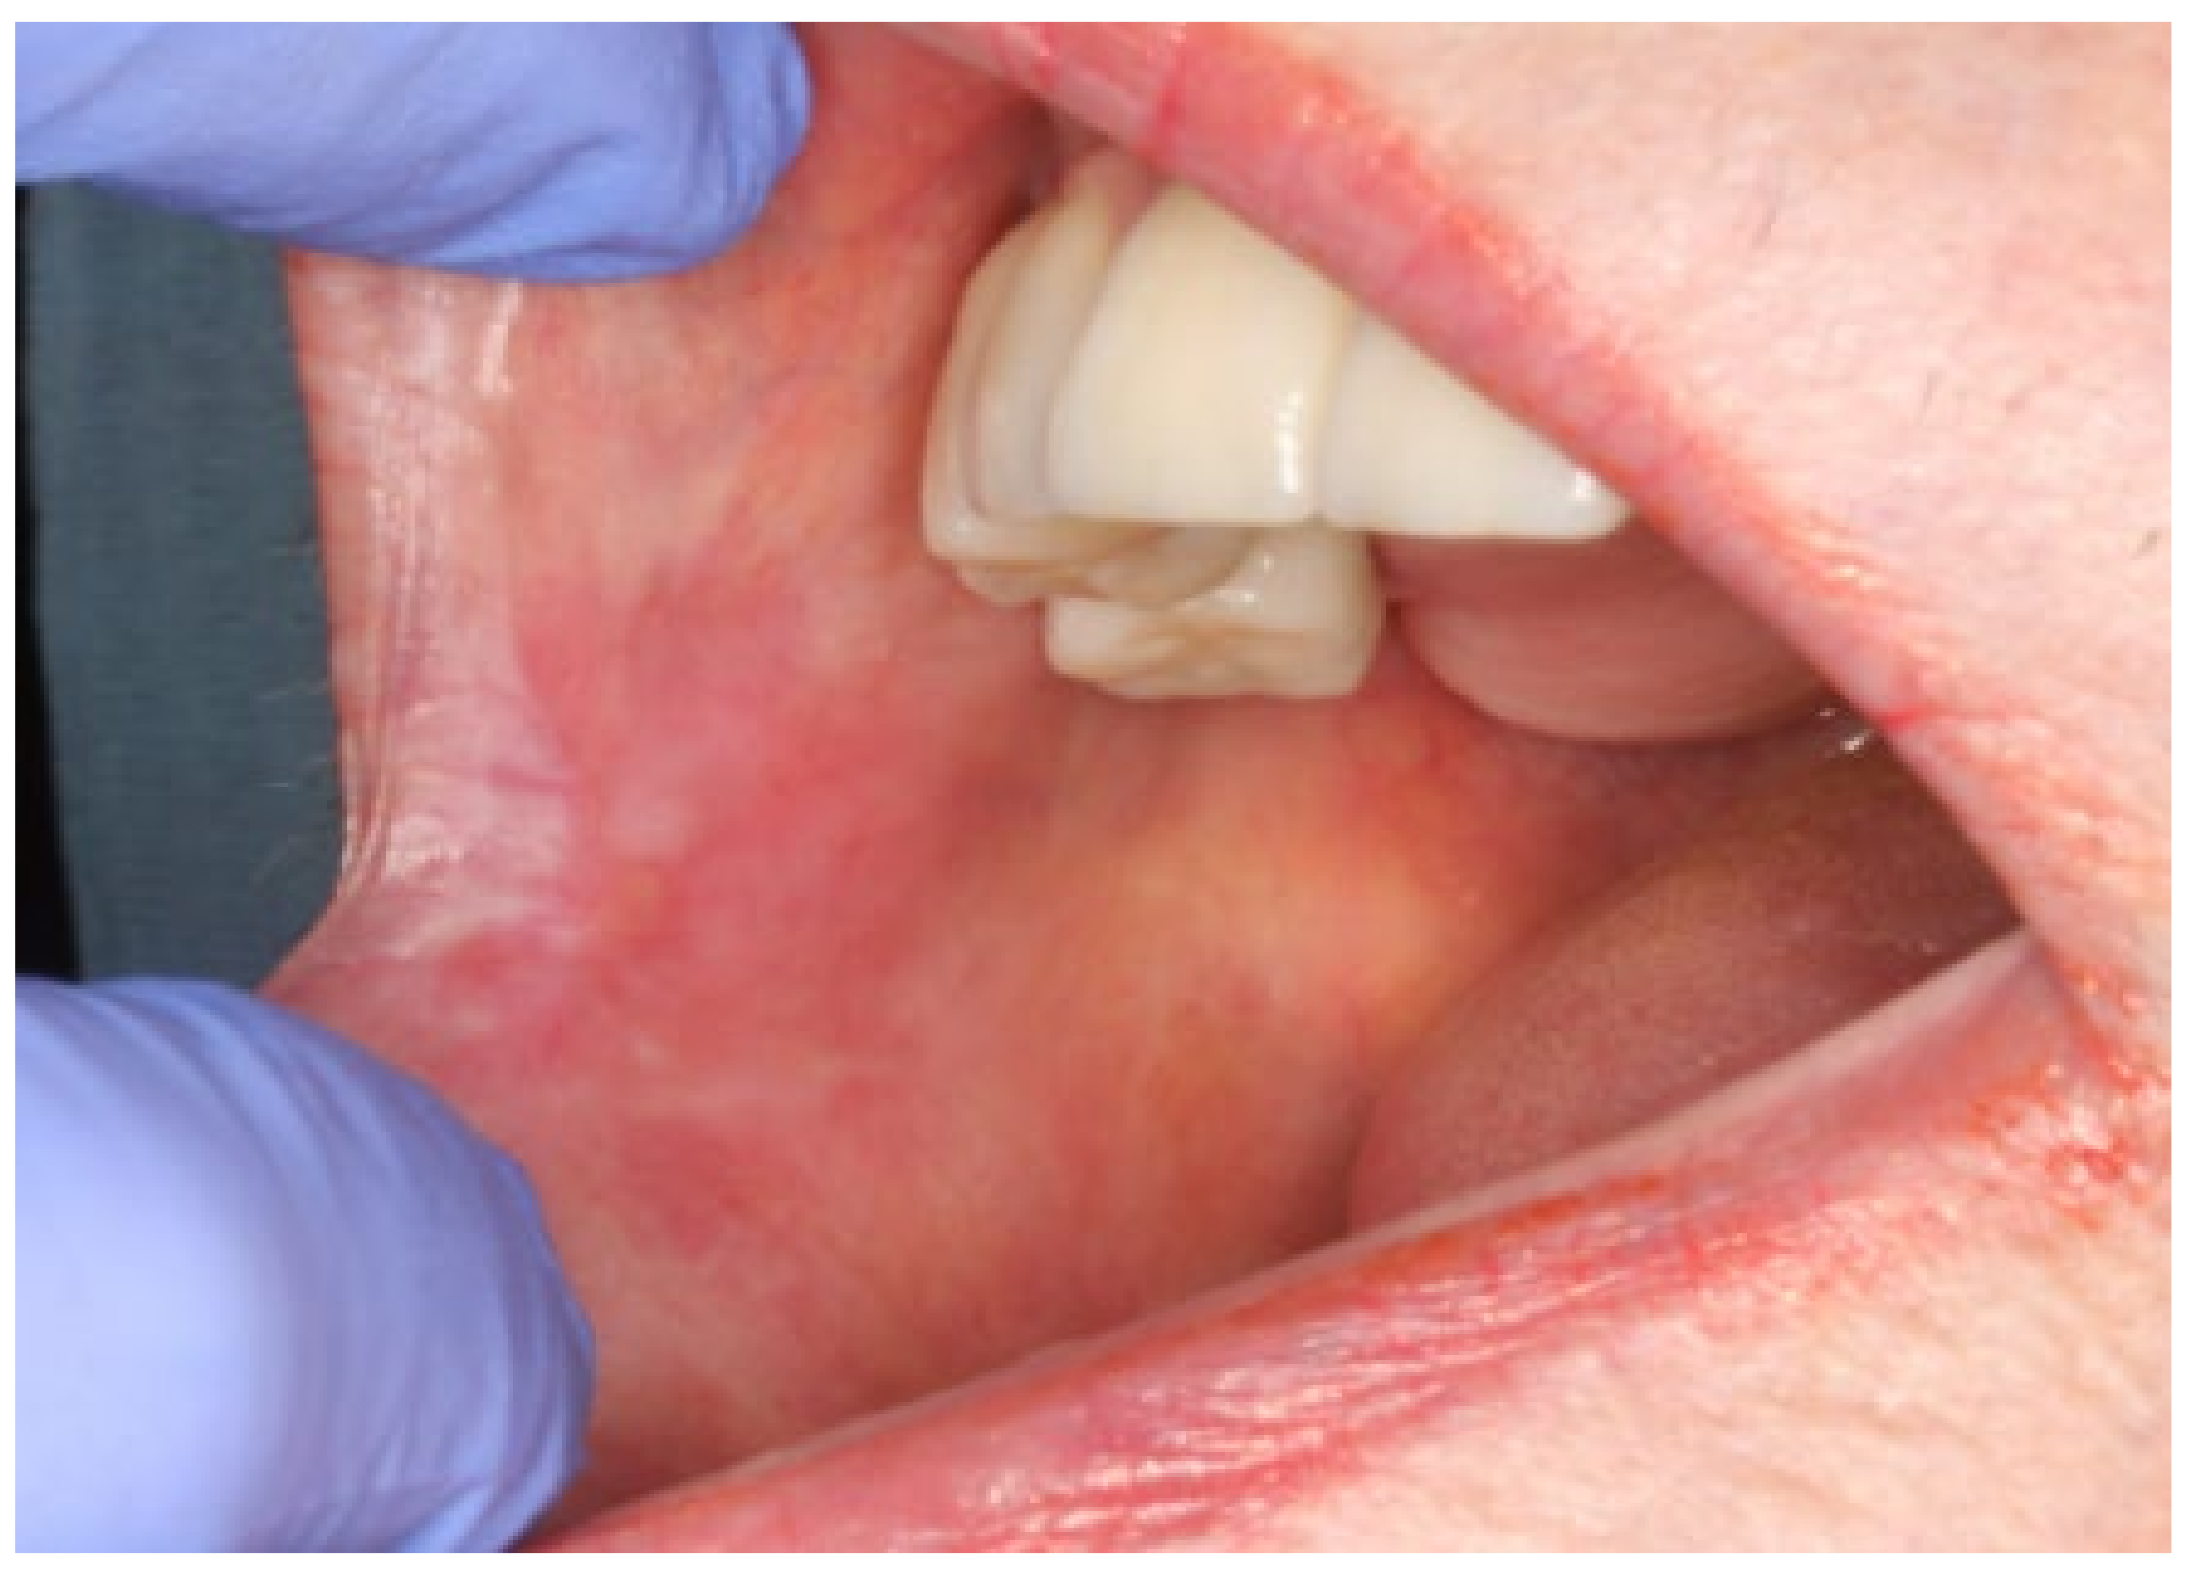

2. Case Presentation